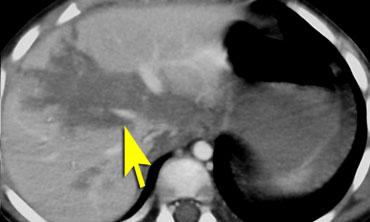

TRÁI: Gãy xương kiểu vỏ trứng ở một trẻ tử vong do chấn thương não sau khi bị ném từ trên cao. PHẢI: Gãy xương sọ ở trẻ bị lạm dụng.

Gãy xương sọ

Gãy xương sọ là chấn thương thường gặp trong lạm dụng trẻ em, nhưng cũng phổ biến trong chấn thương do tai nạn.

Các hình thái gãy xương sọ gợi ý lạm dụng trẻ em bao gồm:

- Gãy xương nhiều mảnh kiểu “vỏ trứng”

- Gãy lún xương chẩm

Hộp sọ của trẻ sơ sinh khá đề kháng với chấn thương, vì vậy bất kỳ gãy xương nào không phù hợp với bệnh sử đều cần đặt ra câu hỏi về chấn thương không do tai nạn.